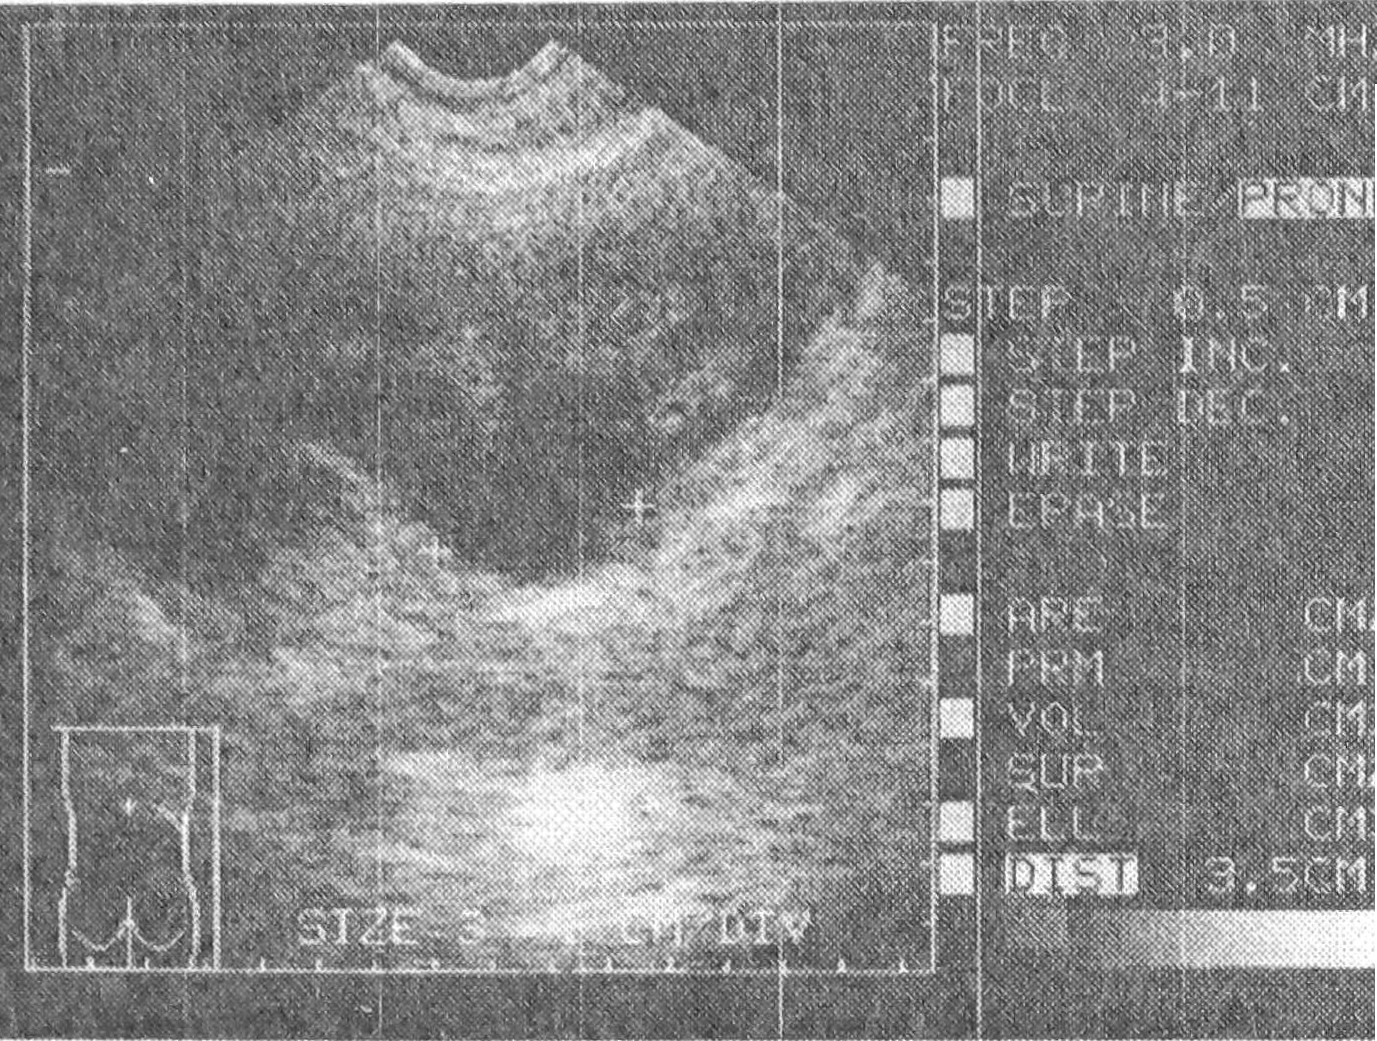

Известно, что клиническое течение опухолей мочевого пузыря и предстательной железы чаще всего осложняется прогрессирующим нарушением уродинамики верхних мочевых путей и вторичным хроническим пиелонефритом в связи с блокадой мочеточниковых устьев. Указанные осложнения чаще всего обусловливают летальный исход при инфильтрирующих опухолях и оказывают существенное влияние на выбор метода их лечения. Ретенционно-обструктивные изменения верхних мочевых путей различной выраженности, характеризующиеся одно- или двусторонним поражением, были выявлены у 30,9% больных с новообразованиями мочевого пузыря, из них в стадии Т2 — у 23,7%, Т3 - 60,3% и Т4 - у 81,8% (рис. 4). Обструкция мочеточников вследствие инфильтрирующего роста опухоли и ретенционные изменения в верхних мочевых путях являются частыми причинами развития острого пиелонефрита. Причинами же развития воспалительных осложнений после оперативного вмешательства по поводу рака мочевого пузыря, как правило, служат операционная травма, дефект выполнения уретероцистоанастомоза, развитие пузырно-мочеточникового рефлюкса и наличие дооперационной ретенции мочи. В случаях обструктивной нефропатии, вызванной блокадой устья мочеточника новообразованием мочевого пузыря, нами применялась разгрузочная чрескожная пункционная нефростомия (ЧПНС) под ультразвуковым контролем (рис. 5). ЧПНС позволяет изучать ренальную функцию при азотемии, обусловленной хронической почечной недостаточностью, и особенно информативна в случаях “немой” почки, являясь при этом единственным методом получения изображения, тогда как ретроградные способы визуализации и дренирования верхних мочевых путей не всегда выполнимы и информативны [3]. При условии значительного расширения чашечно-лоханочной системы на этапе освоения этого исследования мы пользовались методом Goodwin, согласно которому дренирующая трубка вводится непосредственно по просвету пункционной иглы, но в последующем, применяя стандартные нефростомические наборы, стали считать более безопасным и эффективным использование техники Сельдингера.

Рис. 5. Ультрасонограмма почки в момент пункции чашечно-лоханочной системы (cтрелкой указано направление пункционного хода и кончик иглы в нижней чашечке).